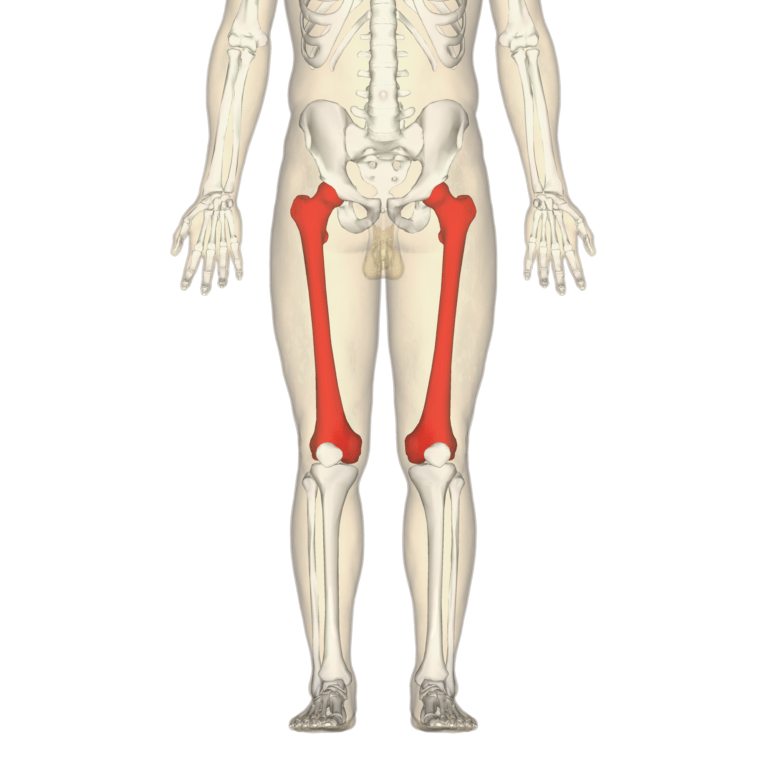

En plus d’être le plus long, le fémur est également l’os le plus résistant du corps humain.

Si, par exemple, on étire de la même manière un fémur humain et un morceau de béton, l’os résistera plus longtemps avant de casser.

Par ailleurs, un fémur peut supporter près de 30 fois son poids, même si cette aptitude concerne surtout les os d’individus très jeunes. En effet, avec l’âge, le col du fémur tend à se fragiliser, notamment à cause des effets d’une maladie nommée ostéoporose.